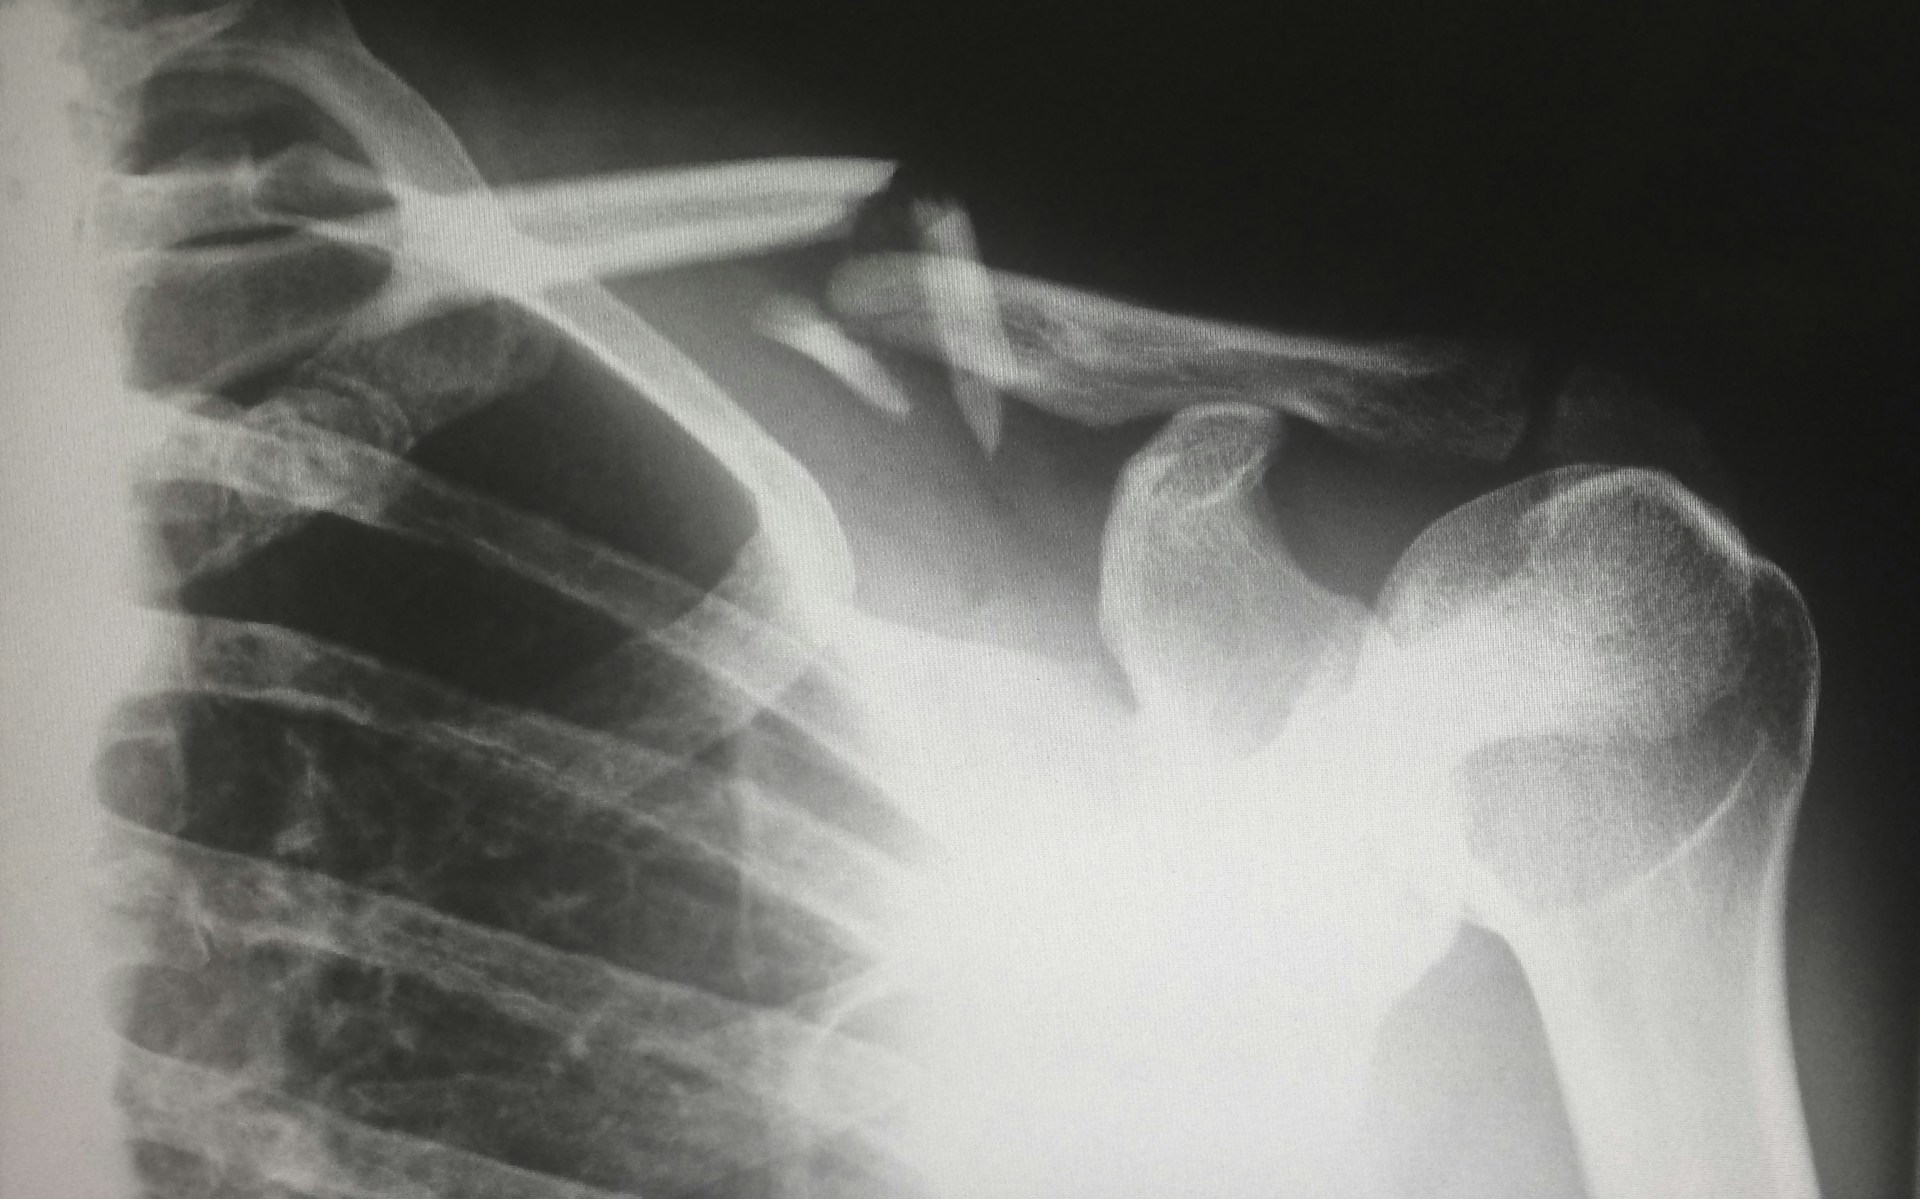

Эксперты портала здоровое-питание.рф рассказали, что это хроническое заболевание обмена веществ, которое может проявляться как клинический синдром при других болезнях. Оно характеризуется снижением плотности костей и увеличением их ломкости, что повышает риск переломов.

Каждый год более 300 000 человек страдают от переломов бедра, связанных с остеопорозом. У пациентов с такими травмами уровень смертности на 12-20 % выше, чем у людей того же возраста и пола без переломов.